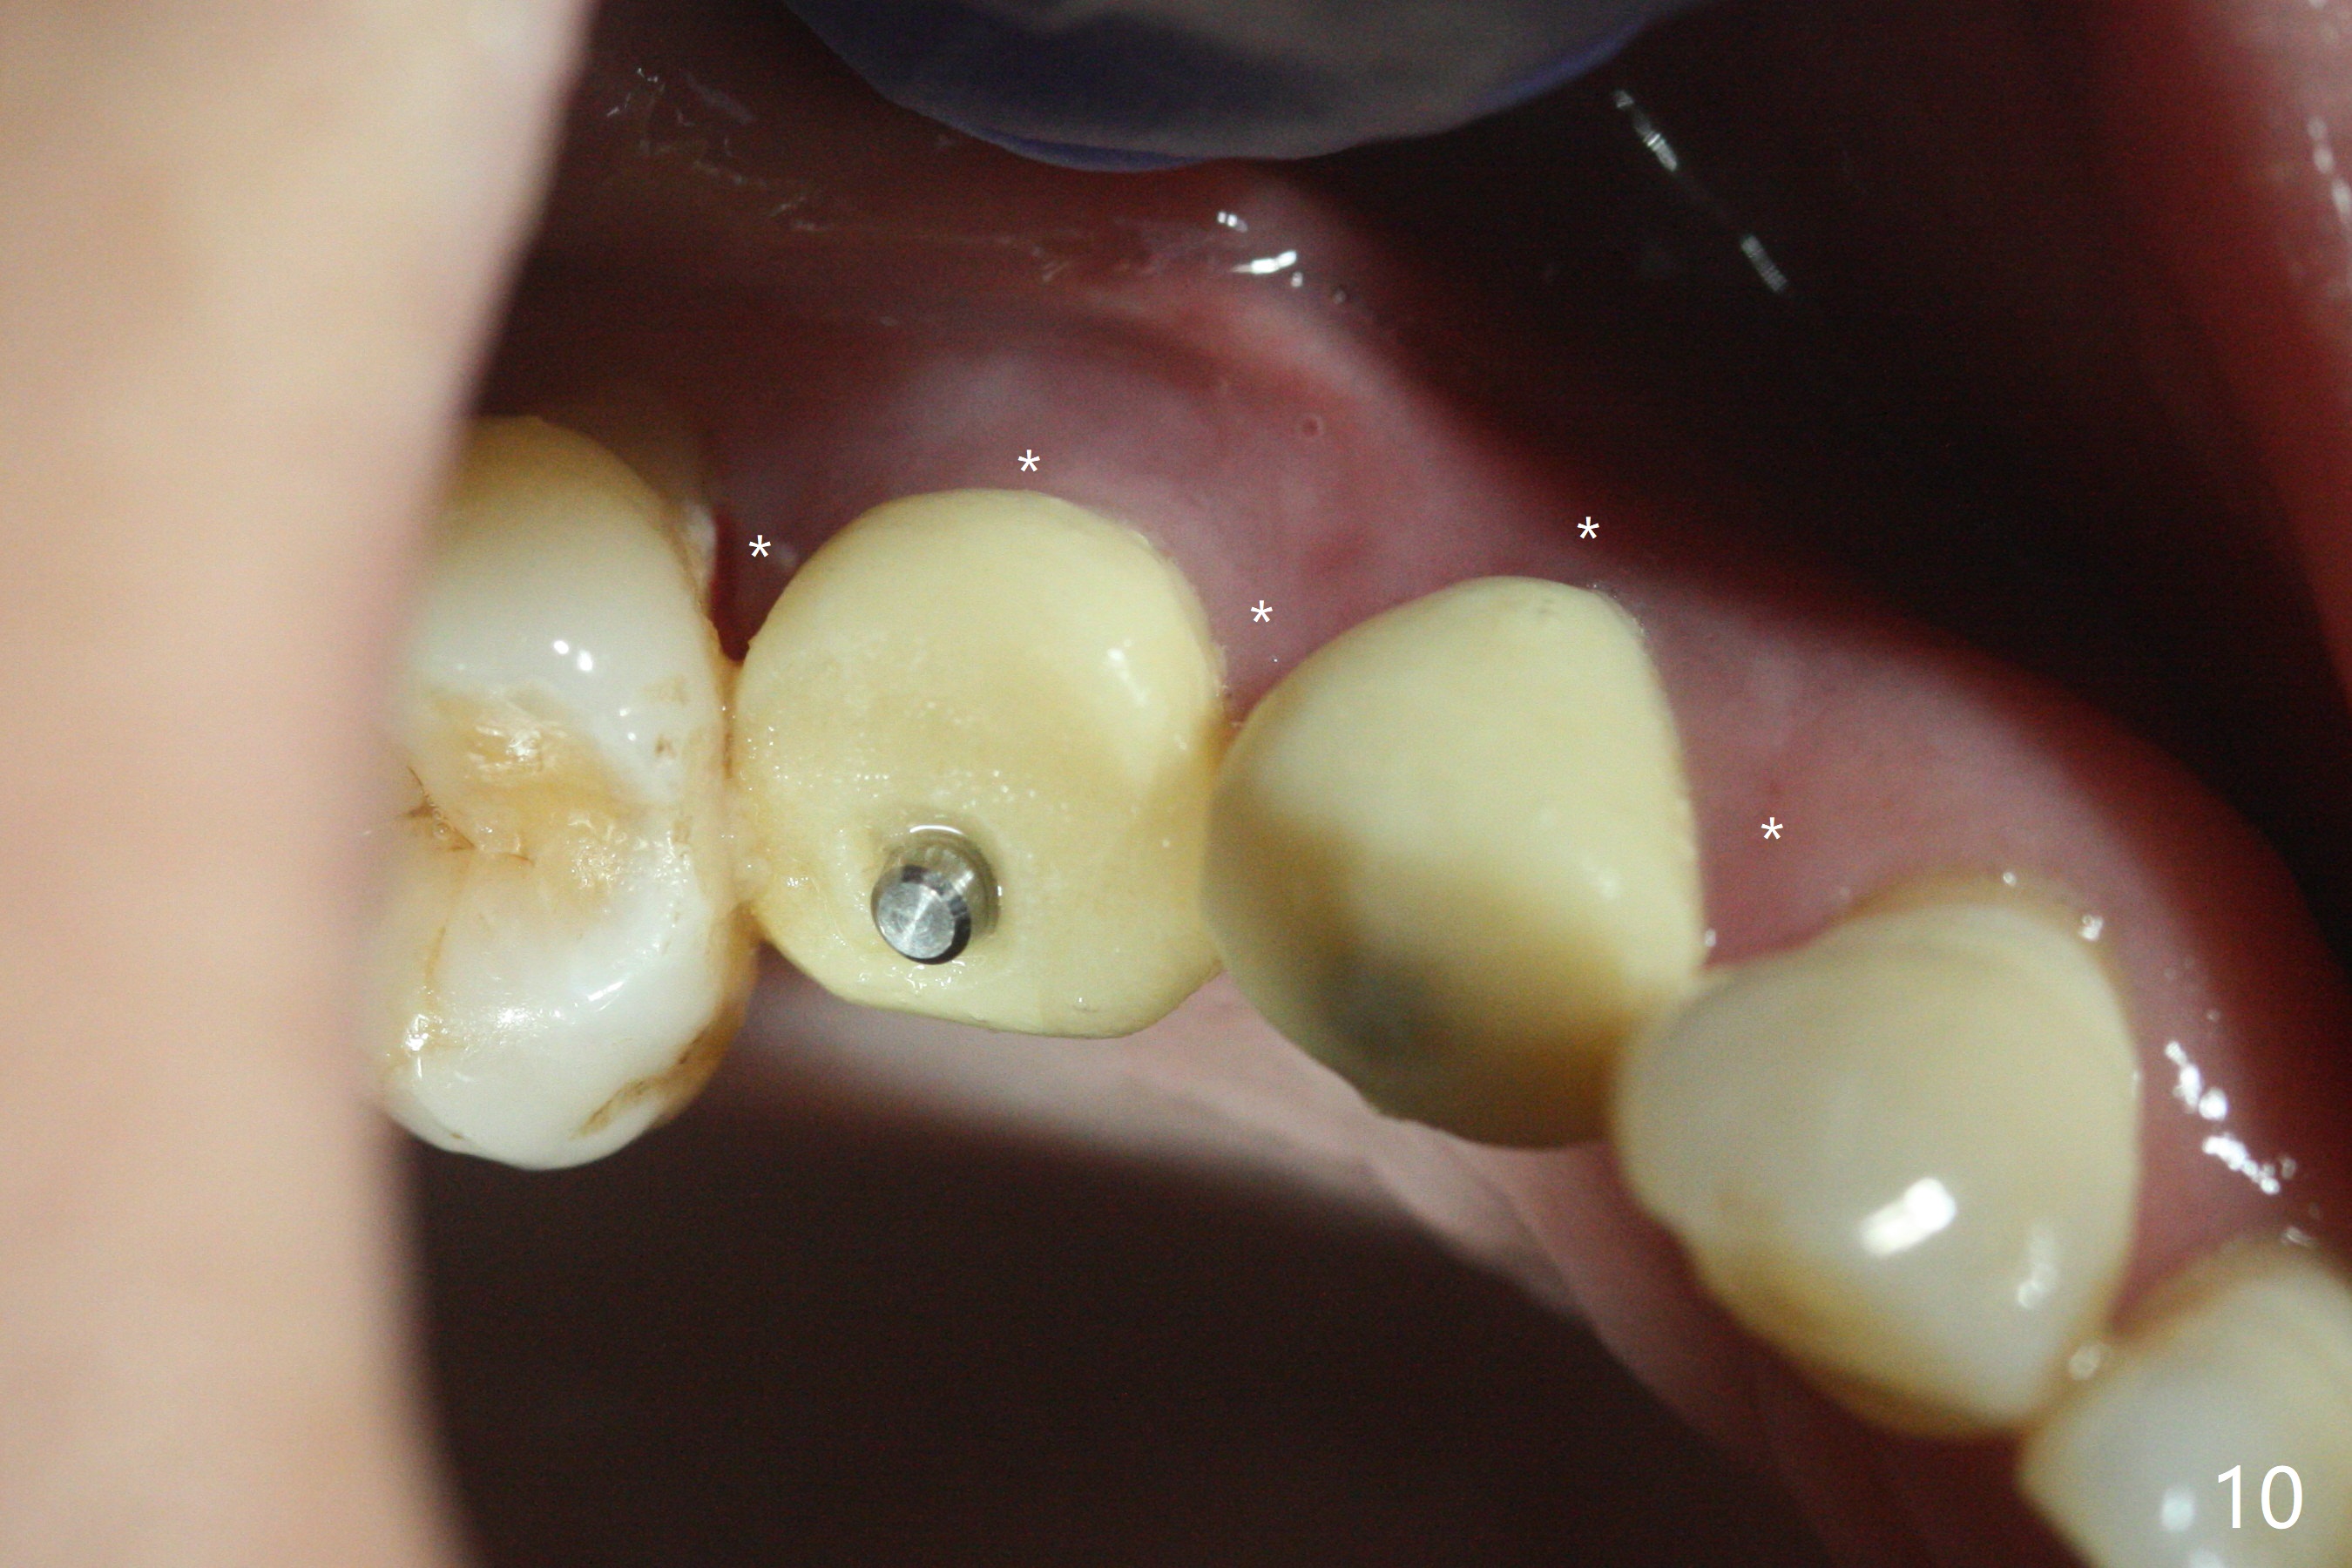

术前CT显示右上4牙槽骨比5窄(图一,二),3.5毫米植体比较合适,况且牙龈厚,基台长的一段式植体显得得当。为了取得最好的植体方位,4先拔除(图三),种植(图四),调整后者深度后,拔除5(术前征求病人同意),开始钻洞(图五),完成种植(图六)。粘性骨粉不仅放置于植体周围,而且6牙根近中(图七),4/5牙槽嵴和龈乳头(P)之间,减少术后龈乳头萎缩(图八:*)。制作两个分开临时牙冠,有利于维持龈乳头。对于病人来说,临时牙冠帮助咀嚼,而对侧拔牙创无法吃饭。术后3个月两个分开临时牙冠(其中一个龈方移位(图九:箭头)保持龈乳头(*)和牙龈外形(图十:*)。临时牙冠取出后,调整基台高度,少量钛屑(不妨大局)附着在健康的牙龈沟(图十一),再次显示两个基台之间龈乳头(图十二:*),衬里,修整的临时牙冠又插回牙龈沟(图十三:箭头),继续维持软组织形态,准备一个月后,调整基台边缘(图十二:箭头),取模。术后五个月大部分骨粉依然保留在植体和邻牙周围,龈乳头退缩不多(图十四: P)。三个月后(术后六个月)钛削无影无踪(图十五,与图十一对比))。永久性牙冠周围空间慢慢会消失(图十六,使用临时性胶水)。